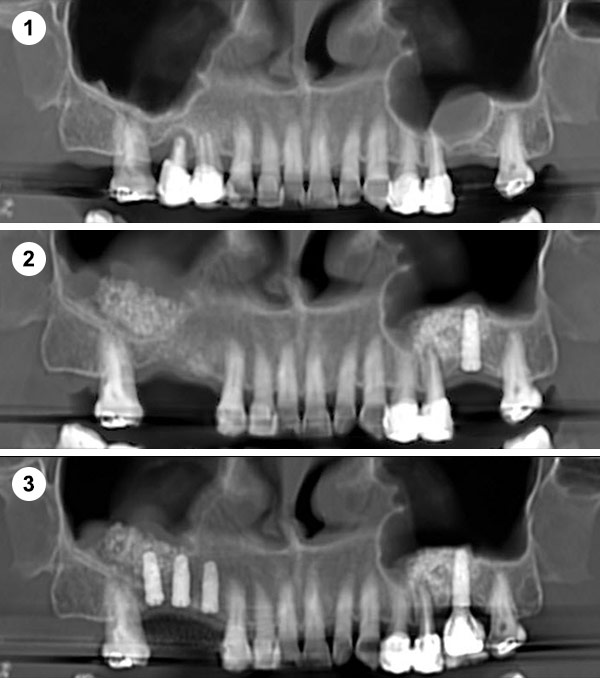

¿Qué es la Elevación Traumática?

Se realiza a través de una apertura lateral en la pared del seno maxilar (ventana lateral). Este enfoque permite un acceso directo a la membrana sinusal para su elevación.

Indicaciones: Se emplea en casos donde la cantidad de hueso residual es muy escasa (<5 mm) o cuando se necesita un aumento significativo del volumen óseo.

Permite una visualización directa y control del procedimiento. Útil para grandes reconstrucciones óseas.